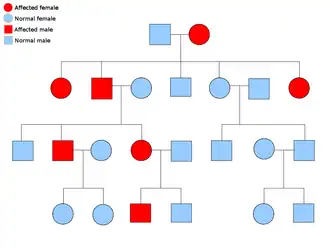

Two copies of every gene are present in all cells of the body and each one is called an allele. Most cancer syndromes are transmitted in a mendelian autosomal dominant manner. In these cases, only one faulty allele has to be present for an individual to have a predisposition to cancer. Individuals with one normal allele and one faulty allele are known as heterozygous. A heterozygous individual and a person with two normal alleles (homozygous) will have a 50% chance of producing an affected child.[9] The mutation in the inherited gene is known as a germline mutation and a further mutation in the normal allele results in the development of cancer. This is known as Knudson's two-hit hypothesis, where the first hit of the gene is the inherited mutation and the second hit occurs later in life.[2] As only one allele needs to be mutated (as compared to both in so-called "sporadic cancers"), the individual has a higher chance of developing the cancer than the general population.[10]

Less often, syndromes may be transmitted as an autosomal recessive trait. Both alleles of a gene must be mutated in autosomal recessive disorders for an individual to have a predisposition to cancer. A person with two recessive alleles is known as homozygous recessive. Both parents must have at least one faulty allele in order for a child to be homozygous recessive. If both parents have one mutant allele and one normal allele (heterozygous) then they have a 25% chance of producing a homozygous recessive child (has predisposition), 50% chance of producing a heterozygous child (carrier of the faulty gene) and 25% chance of produced a child with two normal alleles.[9]